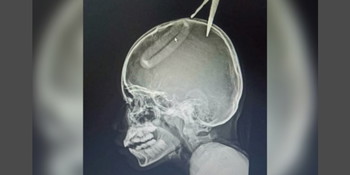

It was found that the pair of scissors was embedded about an inch (2.5cm) deep in her skull.

The blade perforated the skull of the 10-year-old girl, who goes by the name Face, reported Thai publication Thaiger.

It was found that the pair of scissors was embedded about an inch (2.5cm) deep in her skull. It had nearly pierced a nerve but did not strike any vital parts of the brain.

Doctors successfully removed the object, and the girl was warded at the hospital for two days before being discharged to recuperate at home.